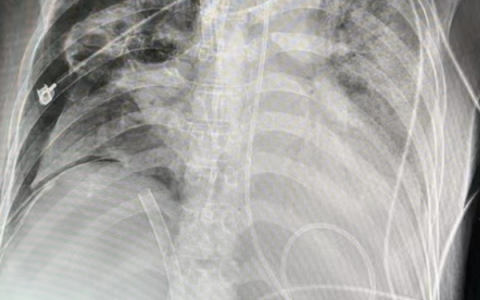

俯卧位对肺实变的影响

俯卧位前后对比 使用EIT来查看 经验:俯卧位使用呼吸机时候,提供一定的PEEP和驱动压,不要快速下降,等待肺完全张开后调整压力。不要只关注二氧化碳分压的水平。